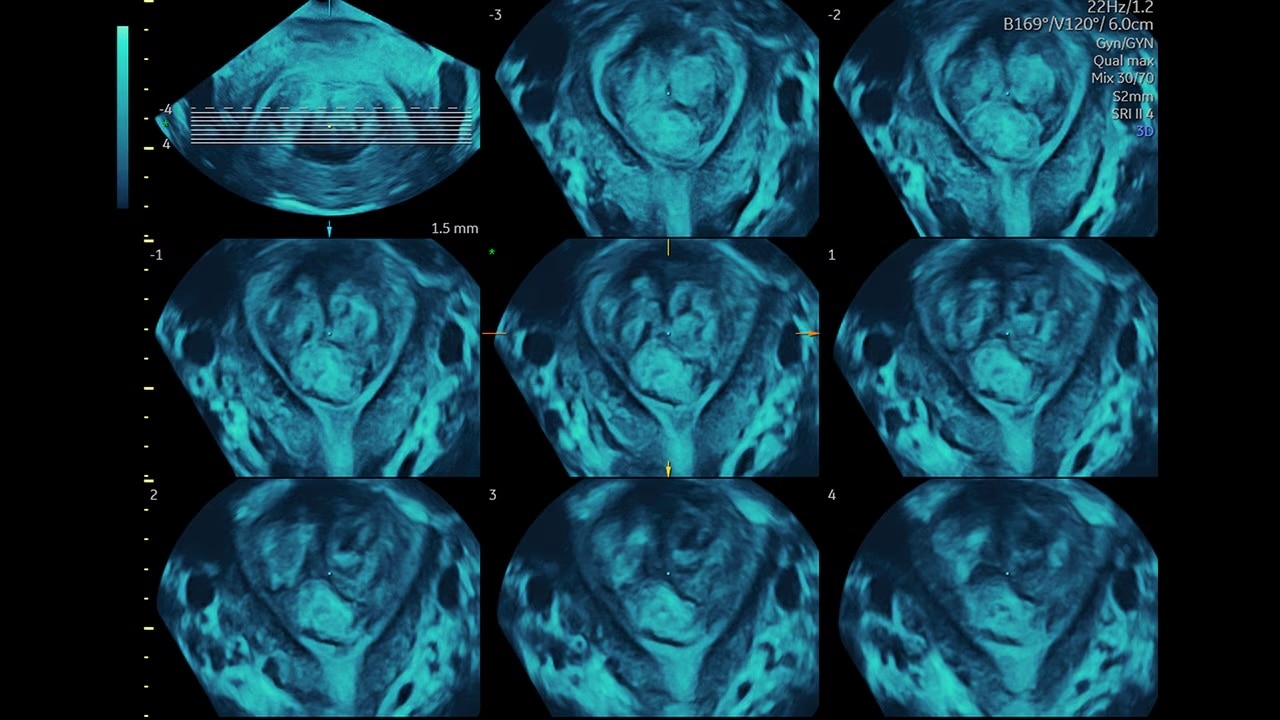

Obtain the coronal plane of the Uterus in ½ the time

Identify fibroids 88% of the time with Fibroid Mapping